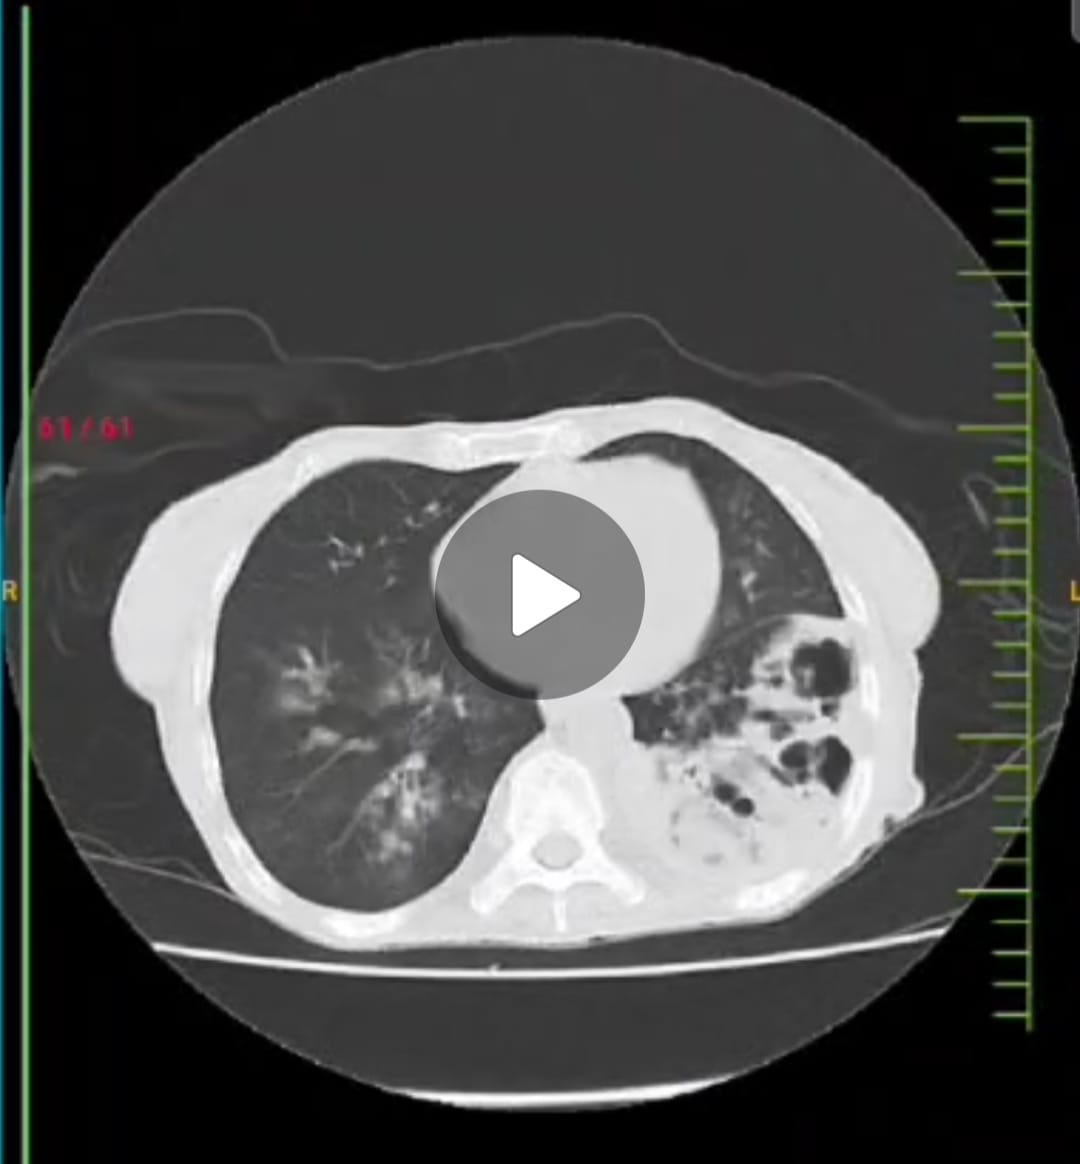

60F With Multiple lower lobe cavitation lesions with apparent pleural involvement.  Thanks for sharing this. Yes there's a possibility that she's loosing blood through her stools as a result of slow GI bleed. Can you share the image of the teeth? Since when was it noticed?

PPM 1 - @PPM7, PPM2, PPM9 Let's try to do an Ultrasound guided left lower pleural aspiration in the morning today ASAP.

PPM 7 - Spoke to PPM11 and PPM12. Sir told that FNAC wasn't done till now for that type of cavities,  and if needed their PGs will guide for USG guided FNAC, and asked to take opinion of pulmonologist and pathologist.

PPM 1 - FNAC is not for the cavity but the pleural infiltration.  Yes please always involve the pulmonology and pathology.